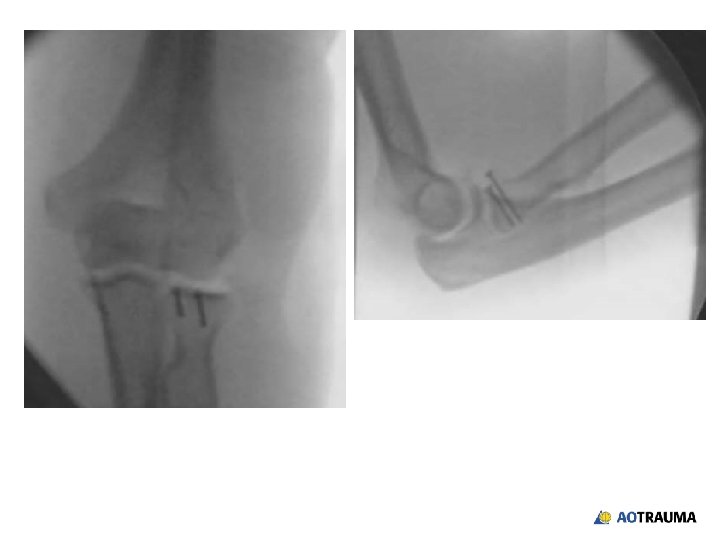

49 -year-old male banker, falls off bike • Fracture dislocation of elbow • Wrist is normal and NV status is ok • Reduction of dislocation reveals elbow pathology

How would you proceed with treatment? 1. Radial head replacement 2. Radial head ORIF 3. Radial head ORIF with coronoid ORIF 4. Radial head ORIF with coronoid ORIF and medial ligament reconstruction 5. Cannot tell and need a CT

Which coronoid fractures should be managed with ORIF? 1. All 2. Large displaced coronoid fractures only 3. Fractures that present with a dislocation 4. Most fractures should be treated if the other stabilizers of the elbow are injured as well